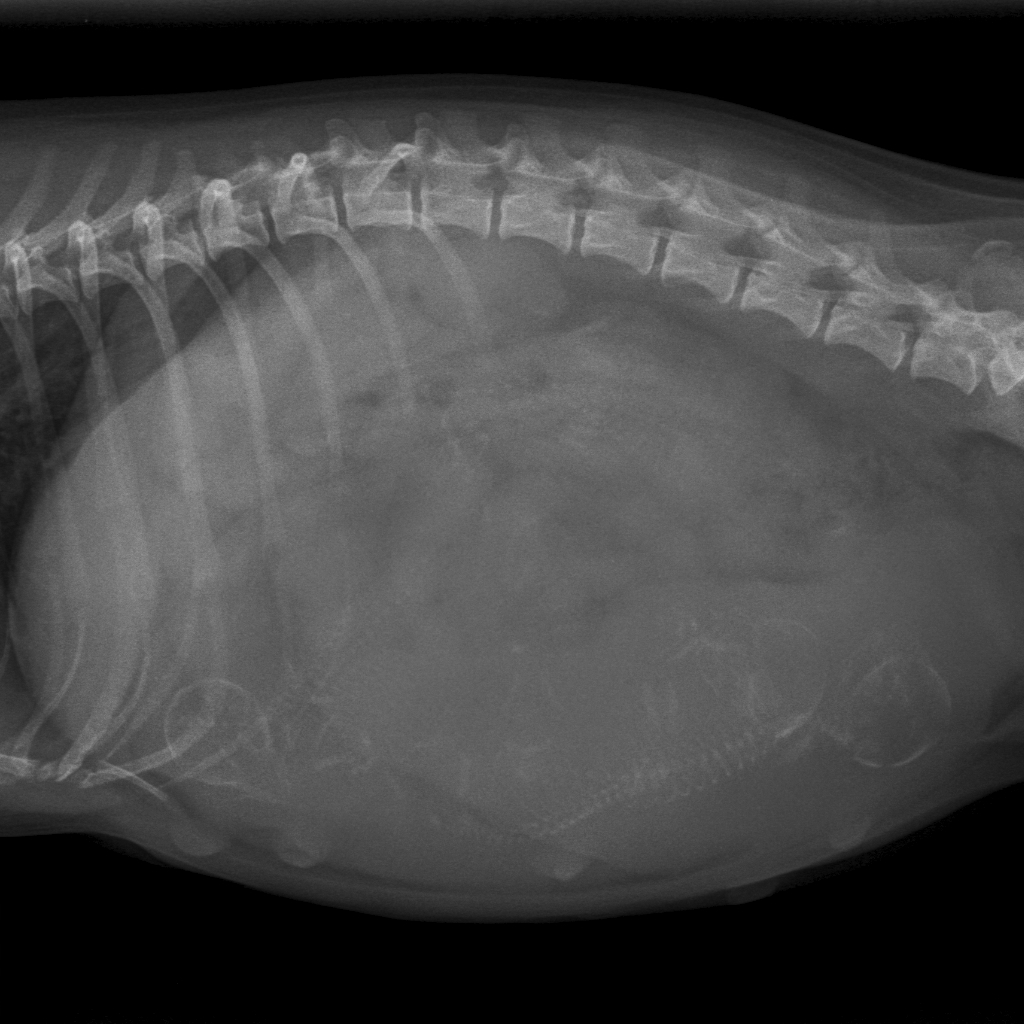

Miss kelly is drachtig. Het chihuahua-teefje van anderhalf jaar kwam op 4 mei op de praktijk voor een röntgenfoto. Haar baasjes wilden namelijk graag weten hoeveel pups ze in haar buik had. Op onderstaande foto's ziet u dat we vier pups tellen, de rode cirkels zijn de kopjes van de ongeboren pups.